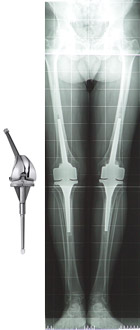

PROTESI VINCOLATE (CON FITTONI) - Si usano nelle revisioni, nelle gravi deviazioni assiali o nelle marcate instabilità del ginocchio. Permettono un ancoraggio e una stabilità dell’impianto maggiori. Sono impianti molto invasivi e per questo motivo il loro utilizzo è riservato a casi particolari.

La decisione di essere sottoposti a un intervento di sostituzione protesica del ginocchio dovrebbe essere presa dal paziente stesso insieme al chirurgo ortopedico, al medico di base e alla famiglia sulla base di molteplici fattori; innanzitutto i sintomi che portano a tale decisione devono essere severi. Non esistono restrizioni assolute in termini di età o di peso, ma sicuramente le condizioni generali del paziente devono essere attentamente valutate.

Un importante fattore nella decisione finale di essere sottoposti a questo tipo di intervento è comprendere ciò che si può e non si può fare con una protesi di ginocchio. Più del 90% dei pazienti che vengono sottoposti a protesizzazione di ginocchio riferiscono una drastica riduzione del dolore al ginocchio e un significativo miglioramento nella capacità di svolgere le attività più comuni della vita quotidiana. Ma questo intervento non permetterà di fare più di quanto si poteva prima di sviluppare l'artrosi.

Con un normale uso e attività, ogni impianto protesico comincia un normale processo di usura del polietilene (inserto in plastica tra le due componenti metalliche) che l’aumento del peso o eccessive attività possono accelerare e portare più precocemente all’inevitabile mobilizzazione dell’impianto e quindi alla necessità di una sua revisione (sostituzione). Per questo, la maggior parte dei chirurghi sconsigliano attività come la corsa, i salti o, in generale, tutti quegli sport ad alto impatto per il resto della vita dopo l'intervento chirurgico. È fondamentale, quindi, che il paziente abbia delle aspettative realistiche prima di sottoporsi a un intervento di protesizzazione del ginocchio.

Attualmente, oltre il 90% delle moderne protesi totali di ginocchio sono ancora ben funzionanti 15 anni dopo l'intervento chirurgico. Modificando lo stile di vita e le attività (alcune di quelle concesse sono la camminata illimitata, il nuoto, il golf, il trekking leggero, la bicicletta, il ballo liscio o altri sport a basso impatto) si può contribuire al successo finale del vostro intervento chirurgico.